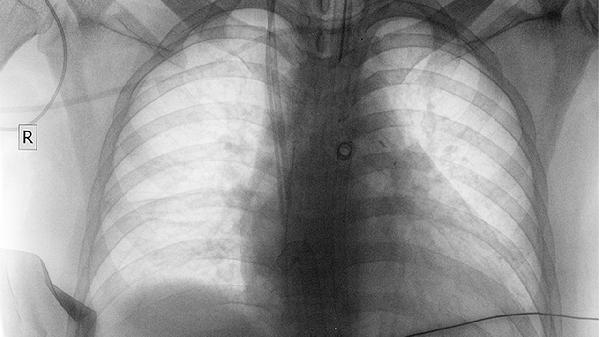

肺癌大多是“拖”出来的,头部出现这3个表现,千万别轻易忽视

肺癌这个"沉默的杀手",往往在早期就悄悄发出警.报信号。可惜很多人把头痛、脸肿当成小毛病,错过了最佳干预时机。今天带你识别那些容易被忽略的头部异常表现,它们可能是肺部在"求.救"。

这些症状虽然不一定都是肺癌,但确实值得提高警惕。特别是长期吸烟者、有肺癌家族史的人群,出现上述表现更要及时做低剂量CT检查。现代医学对早期肺癌的治疗几率很高,关键就在于及时发现那些细微的身体信号。记住,异常症状持续两周以上就该看医生,别让"等等看"耽误了最佳诊疗时机。